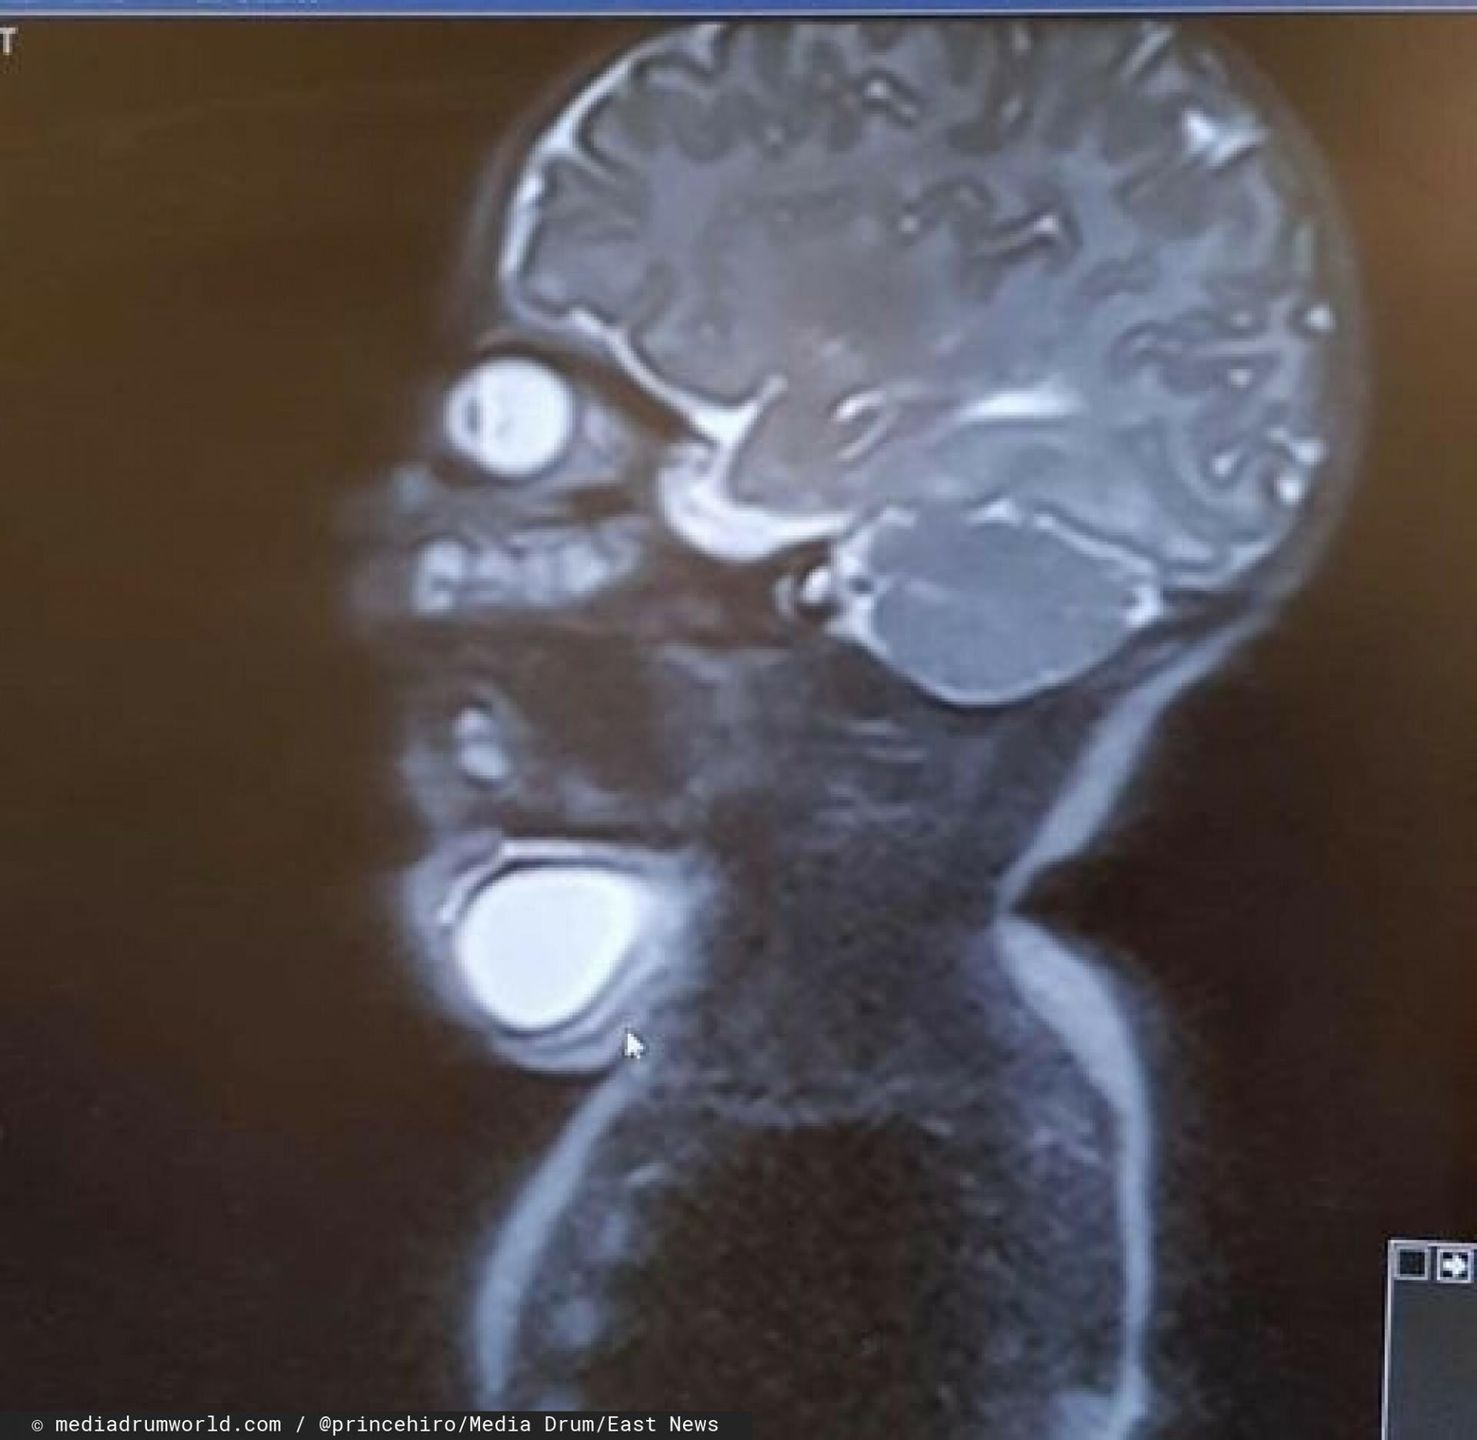

Zdjęcie RTG Hiro

Zdjęcie RTG Hiro © EastNews

Jednak podczas rutynowego badania w 20. tygodniu ciąży lekarz zauważył, że na szyi płodu (tuż pod podbródkiem) tworzy się duża, wypełniona płynem cysta. Po wykonaniu dodatkowych badań okazało się, że był to guz limfatyczny (naczyniak torbielowaty), który bardzo szybko się powiększa. Diagnoza przestraszyła rodziców, którzy bali się o przyszłość swojego dziecka.

Lekarz Katie poinformował ją, że guz ma prawie 6,5 cm średnicy i odsuwa główkę dziecka do tyłu. W związku z tym będzie musiała przejść cesarskie cięcie. Jednak kobieta się nie zdecydowała na tę metodę, ponieważ chciała urodzić naturalnie. Lekarz uszanował jej decyzję i wykonał precyzyjny zabieg jeszcze przed porodem. Wbił igłę przez brzuch Katie, by się dostać do guza płodu i go opróżnił.